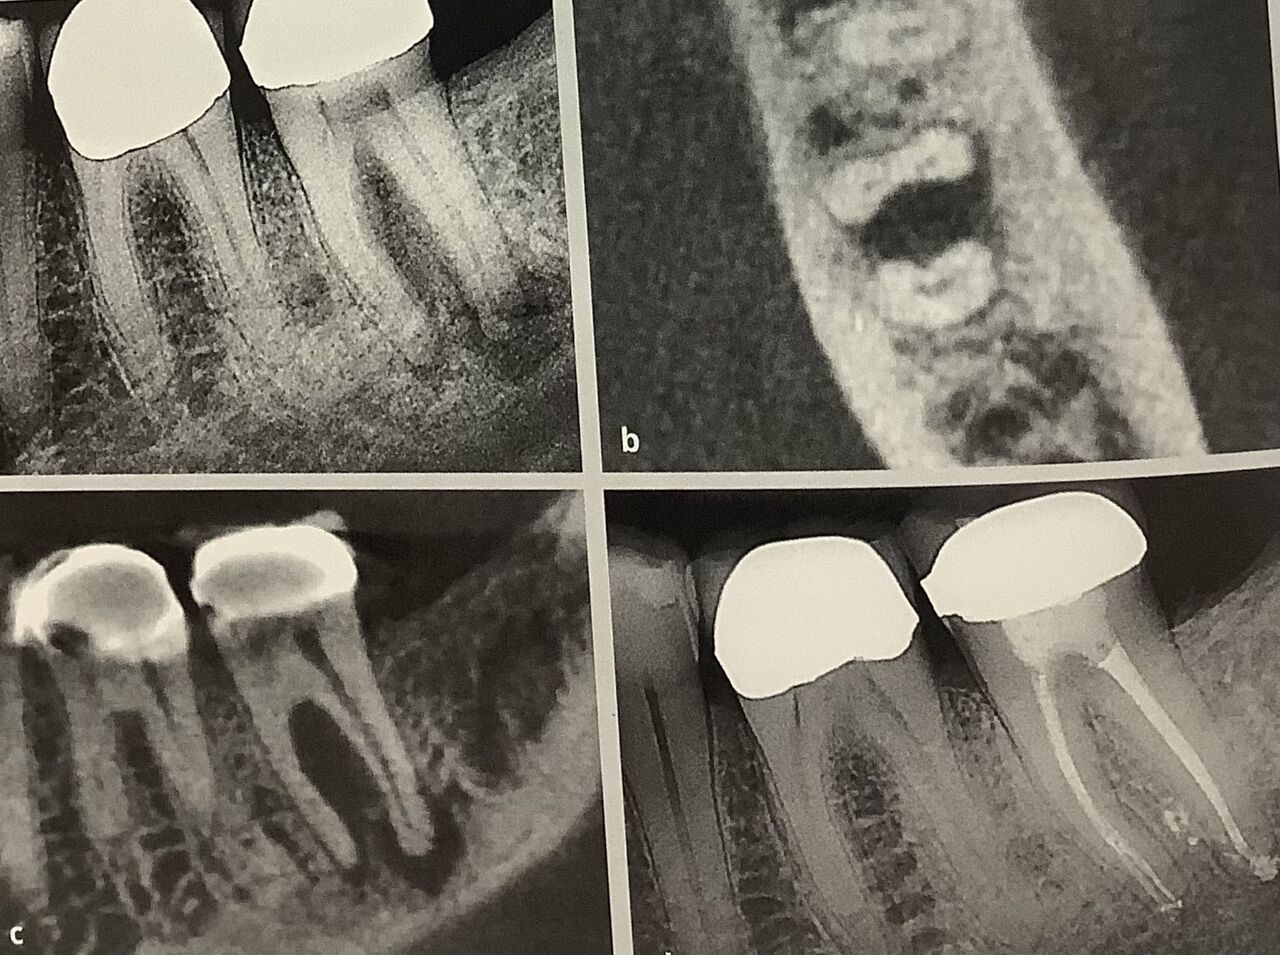

左下の奥歯の神経が死んじゃって、根っこに病気が出来てます。

右のCTを見ると、ウリ、ひょうたん、そら豆みたいにくびれた形でしょう。

ウチマタが薄いんですよ。

気を付けないと、穴が開いちゃいます。

上手な治療ですね。

バッチリと治って、歯も十分に残っています。